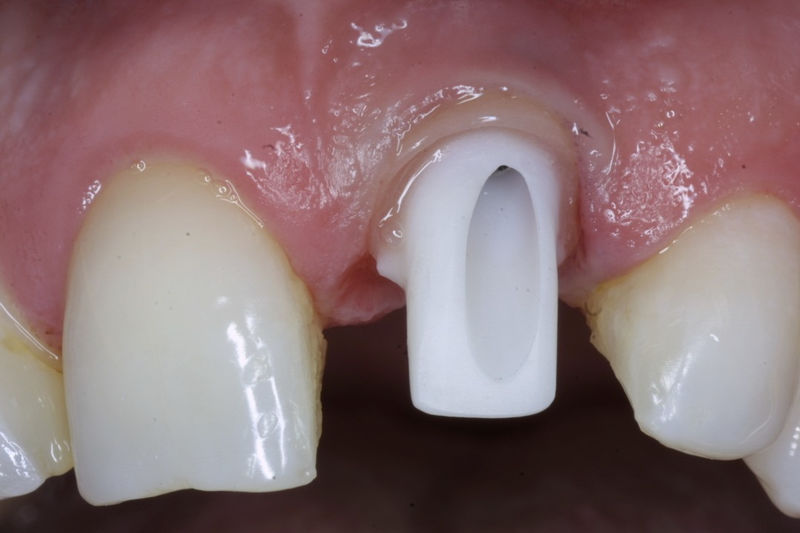

Son estructuras de titanio las cuales se colocan en el hueso y se utilizan para soportar coronas, prótesis fijas, removibles y totales. La colocación de los implantes se hacen previo análisis tomográfico.

Son aditamentos artificiales colocados en la parte interna de la raíz de dientes con tratamiento endodóntico y con amplia destrucción. Usados comúnmente para soportar coronas completas.